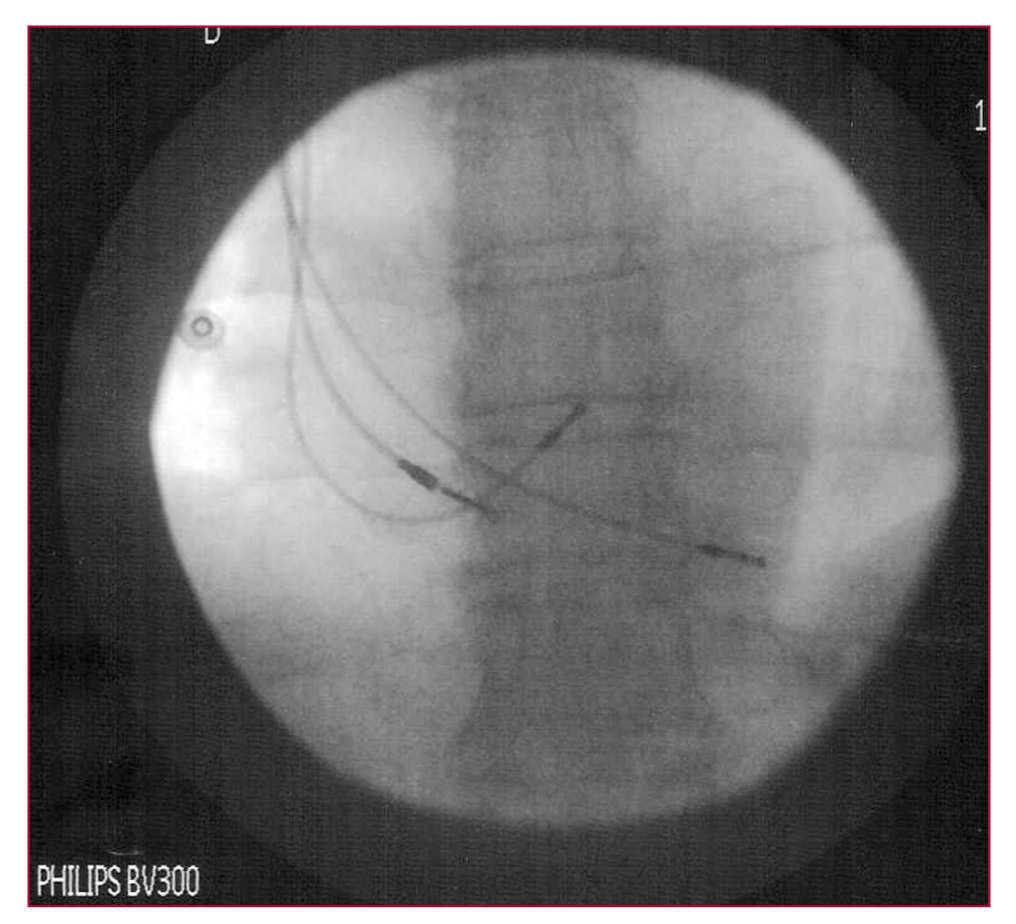

Leads were implanted in the right atrium, in the bundle of His, and, for safety, at the apex of the right ventricle (Figure 4), and connected to the atrial, left ventricular, and right ventricular terminals, respectively, of a biventricular pacemaker generator.

Figure 4. Radiological image of 3 definitive leads placed in the lower interatrial septum, His-bundle, and the right ventricular apex.